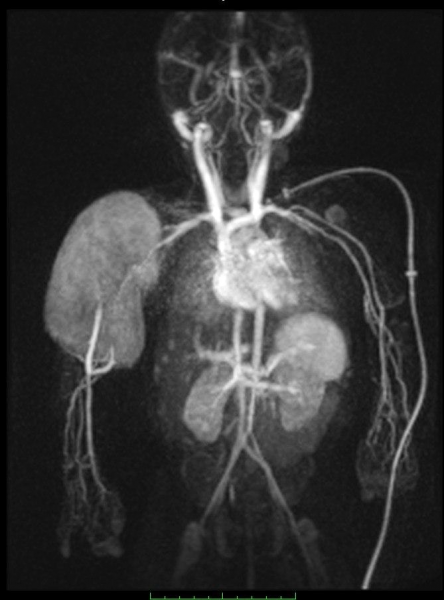

Завдяки передовим технологіям ми маємо можливість проводити МРТ дослідження “всього тіла” (whole body)*, мультипараметричні обстеження головного мозку та простати з наявними програмами МР-трактографії (DTI), МР-спектроскопії, також виконуємо безконтрастну МР-ангіографію інтракраніальних судин, шиї; МР-холангіопанкреатографію, ентерографію, визначення перенавантаження залізом печінки.

*“всього тіла” (whole body) як онкоскринінг чи група overgrowth syndrome.